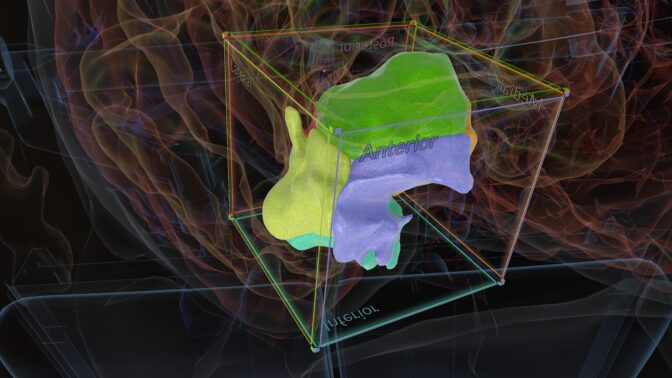

To create digital twins of sufferers’ brains, the Atlas Pathfinder software has adopted MONAI Label, which might help radiologists by mechanically annotating MRI and CT scans to section regular constructions and tumors.

“MONAI Label is the gateway to any healthcare venture as a result of it gives us with the chance to section essential constructions and defend them,” mentioned Dr. Cohen-Gadol. “For the Atlas, we’re coaching MONAI Label to behave because the eyes of the surgeon, highlighting what’s a standard vessel and what’s a tumor in a person affected person’s scan.”

With a segmented view of a affected person’s mind, Atlas Pathfinder can regulate its 3D mind mannequin to morph to the affected person’s particular anatomy, capturing how the tumor deforms the traditional construction of their mind tissue.

Primarily based on the visualization — which radiologists and surgeons can modify to enhance the precision — Atlas Pathfinder suggests the most secure surgical approaches to entry and take away a tumor with out harming different elements of the mind. Every strategy hyperlinks out to the Atlas web site, which features a written tutorial of the operative plan.